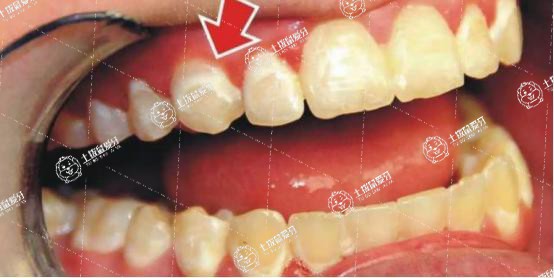

牙齦紅腫怎么快速消腫

牙齦紅腫不存在統(tǒng)一的快速消腫方法。要想消腫應(yīng)根據(jù)病因進(jìn)行處理,常見(jiàn)病因包括牙結(jié)石、智齒冠周炎,可采用洗牙、牙周刮治、沖洗上藥等。

1.如果是因?yàn)榭谇恍l(wèi)生不良導(dǎo)致牙菌斑大量聚集,結(jié)合大量食物殘?jiān)鼜亩纬裳澜Y(jié)石。牙結(jié)石會(huì)對(duì)牙齦產(chǎn)生持續(xù)性刺激從而導(dǎo)致牙齦紅腫,此時(shí)應(yīng)當(dāng)采用洗牙去除牙結(jié)石。

單純的洗牙只能去除牙齦上方的結(jié)石,如果是牙菌斑以及牙結(jié)石殘留在牙齦下方,那么此時(shí)應(yīng)當(dāng)采取牙周刮治。

2.如果本身存在智齒,在智齒周圍的牙齦出現(xiàn)紅腫,形成智齒冠周炎,嚴(yán)重者出現(xiàn)張口受限,應(yīng)當(dāng)用過(guò)氧化氫以及生理鹽水交替沖洗牙周袋,并采用碘甘油涂布。

牙齦紅腫還可能存在其他原因,不建議自行盲目處理,應(yīng)當(dāng)去當(dāng)?shù)蒯t(yī)療機(jī)構(gòu)根據(jù)不同病因選擇相應(yīng)的處理方法,使用藥物需遵醫(yī)囑。